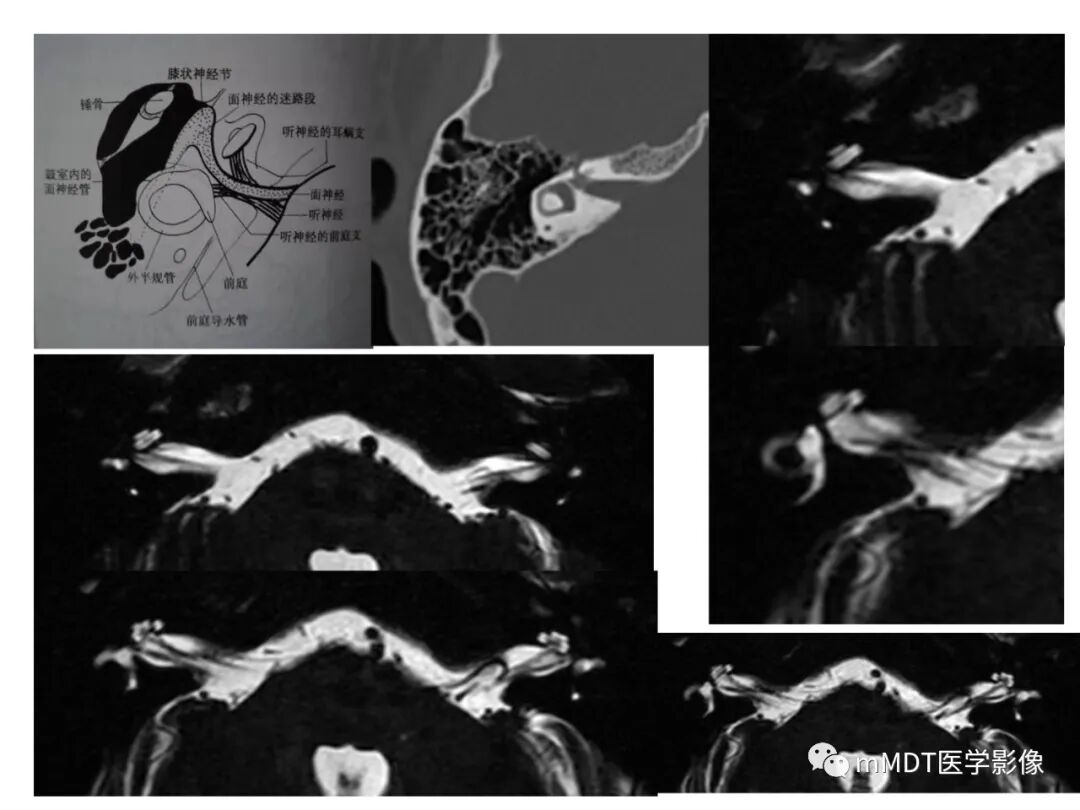

内耳道(internalacoustic meatus)位于颞骨岩部后面中部,自内耳门到内耳道底,内有前庭上神经前庭下神经蜗听神经面神经穿行(触底四神共一门

触底四神共一门

触内耳道底及行向内耳门四神经

面神经(前上)含

•面神经主根(内脏感觉特殊运动及躯体感觉混合成分)

•中间神经(司面神经相关副交感)

蜗听神经(前下)含

•蜗听神经(听觉)

前庭下神经(后下)含

•球囊神经(司静止位置觉及直线加减速度)

•后壶腹神经(单孔)(旋转加速度)

前庭上神经(后上)含

•椭圆囊神经(司静止位置觉及直线加减速度)

•外壶腹神经(旋转加速度)

•上壶腹神经(旋转加速度)

面 听  后球 椭外上